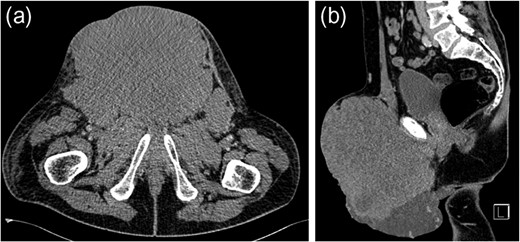

Seminomatous germ cell tumours characteristically affect men in their second-to-fourth decades, presenting as a testicular mass. Metastases when present are usually seen in para-aortic lymph nodes. These tumours are difficult to diagnose clinically and histologically when the presentation is unusual. We describe a seminoma presenting in a 61-year-old male as an inguinal mass with associated lymphadenopathy resembling lymphoma. Past medical history included ipsilateral cryptorchidism and orchidopexy. The tumour responded well to conventional chemotherapy.

Testicular tumours account for approximately 1% of all malignancies in men [1]. Up to 95% of testicular tumours are germ cell tumours (GCTs), which are subdivided into seminomatous and non-seminomatous tumours [2]. Histologically, seminomas may be further divided into three subtypes: classic, anaplastic and spermatocytic. Pure seminomas do not produce a specific tumour marker subset, but by definition have low levels of alpha-fetoprotein (AFP) and can have normal or mildly elevated beta-HCG (beta-subunit of human chorionic gonadotropin) [3]. Risk factors for the development of GCTs include cryptorchidism, Klinefelter's syndrome and testicular dysgenesis [4]. Testicular tumours commonly metastasize along gonadal vessels to the retroperitoneal lymph nodes [5]. Inguinal metastasis from a testicular seminoma is rare and likely related to previous inguinal or scrotal surgery causing disruption in normal lymphatic drainage [6]. We report a case of a massive seminoma presenting with primary inguinal lymph node metastasis in the absence of retroperitoneal lymphatic spread.

Testicular tumours account for approximately 1% of all malignancies in men, and they are the most common solid malignancy that affect males between 15 and 35 years old [2]. Up to 95% of testicular cancers are GCTs and the most common site for metastatic spread is the retroperitoneal lymph nodes. Inguinal lymph node metastasis is a rare occurrence and may be secondary to retrograde extension from significant retroperitoneal metastatic burden [5]. Primary involvement of inguinal nodes may be due to direct tumour invasion into the epididymis, breaching the scrotal wall or extension towards the vas deferens [7]. The large size of the tumour in our case suggests it is highly likely inguinal node involvement was via this route.

However, inguinal metastases have been reported in up to 10% of patients with a testicular tumour who have previously undergone orchidopexy or scrotal surgery [8]. It has been suggested that previous inguinal or scrotal surgery may lead to alteration in the usual patterns of lymphatic drainage. In our case, the history of orchidopexy for cryptorchidism could have been a significant factor for the absence of retroperitoneal lymphadenopathy despite the significant tumour burden at presentation. The overall risk of developing testicular cancer is greater in patients with previous cryptorchidism, occurring in 10% of GCTs [9]. Our case suggests that patients who have previously undergone inguinal or scrotal surgery may have alterations in normal lymphatic drainage leading to rare and atypical presentation of metastatic disease despite high tumour burden.

Ultimately, inguinal lymph node metastasis is a rare direction of spread for seminomatous GCTs. It may be secondary to direct extension of the tumour or alteration in the lymphatic drainage after previous inguinal or scrotal surgery. Although retroperitoneal lymph nodes are the most common site of metastasis in GCTs, alternative directions of spread should be considered in those patients who have undergone previous orchidopexy. Extensive imaging beyond CT for initial evaluation of retroperitoneal lymphadenopathy is unnecessary.